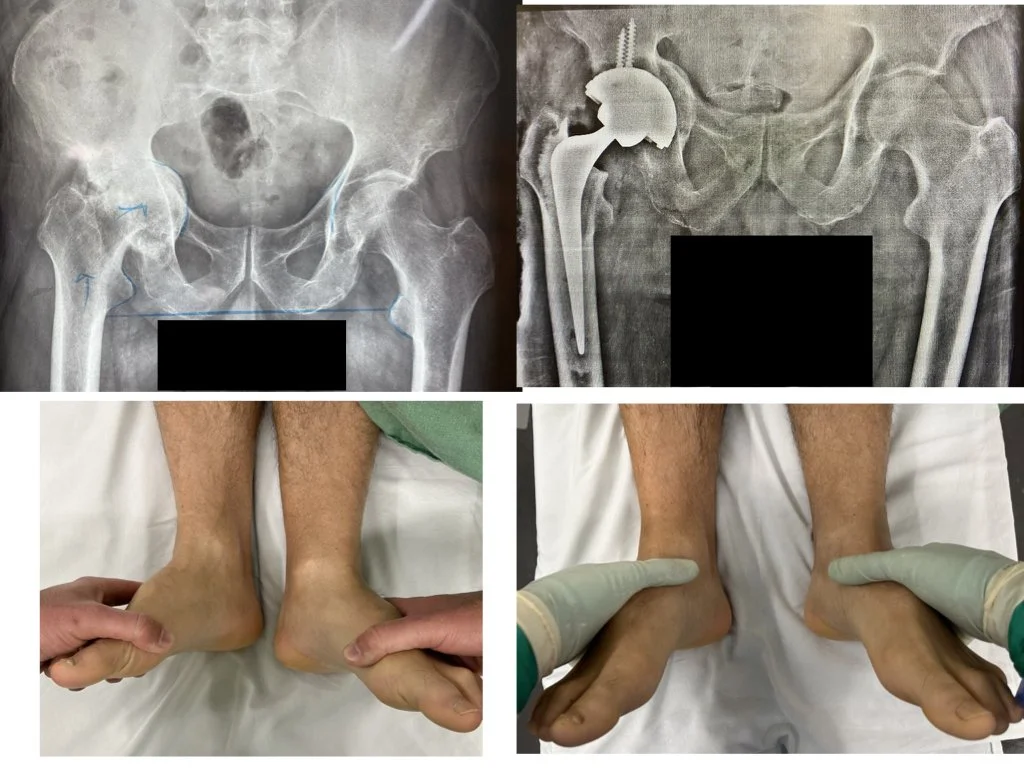

9. Alterações Estruturais e Discrepância de Comprimento

O aparecimento de discrepância no comprimento dos membros inferiores indica progressão de dano cartilaginoso para destruição óssea. O colapso da cabeça femoral e a erosão acetabular resultam em alteração do alinhamento esquelético global, com a pelve adaptando-se à nova geometria articular.

Esta fase representa transição crítica. Enquanto a perda isolada de cartilagem permite várias abordagens terapêuticas, o comprometimento ósseo estrutural limita significativamente as opções. Quanto maior for o atraso após início de alterações ósseas, maior a complexidade cirúrgica, podendo exigir enxertos ósseos, implantes especializados ou procedimentos reconstrutivos adicionais.

Correção da diferença de comprimento devido à artrose severa do quadril direito com uso de enxerto, parafusos e implante especial no acetábulo.